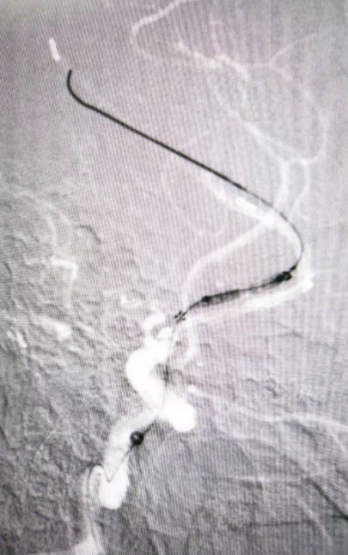

药物球囊扩张(2.0 mm×20 mm)

扩张前带涂层的球囊(左图)与扩张后释放完涂层的球囊(右图)